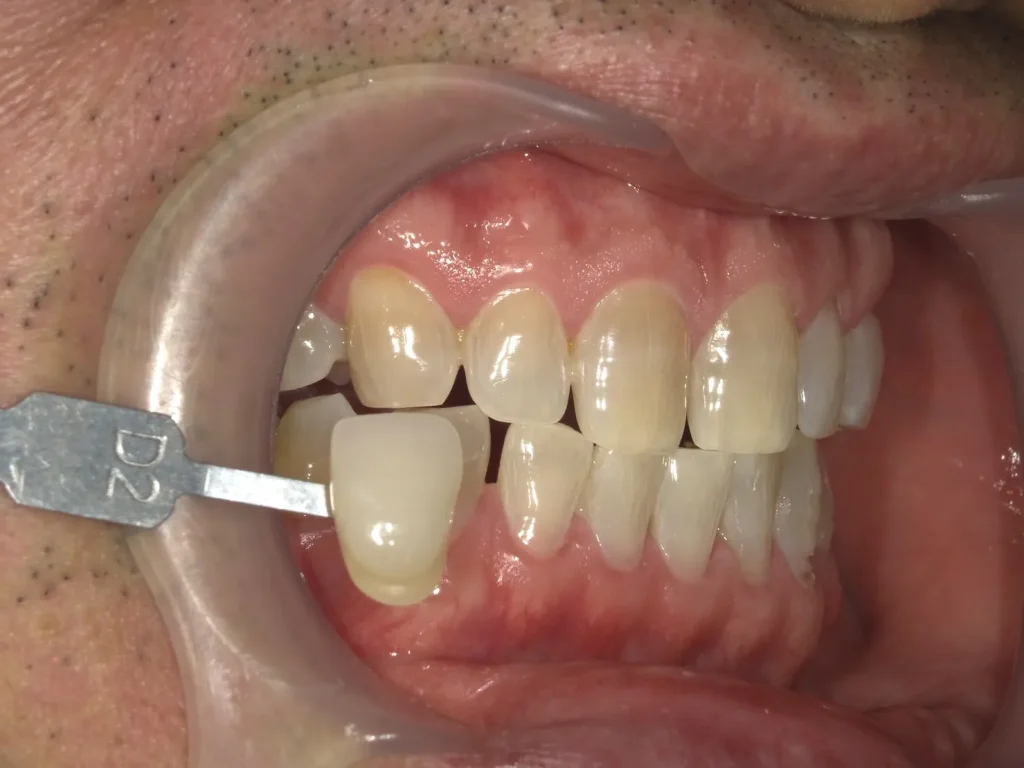

術前術後写真

歯科衛生士からのコメント

仕事の帰りが遅く、最初は一日30分くらいずつのホームホワイトニングでしたが、どんどん白くなるのが楽しくなり、途中から1.5時間くらいはがんばりました。

ホームホワイトニングの時間を延ばした直後から、少し違和感とシミを感じたそうですが、気になる程でもなかったとのことなので、そのまま継続してしてもらいました。